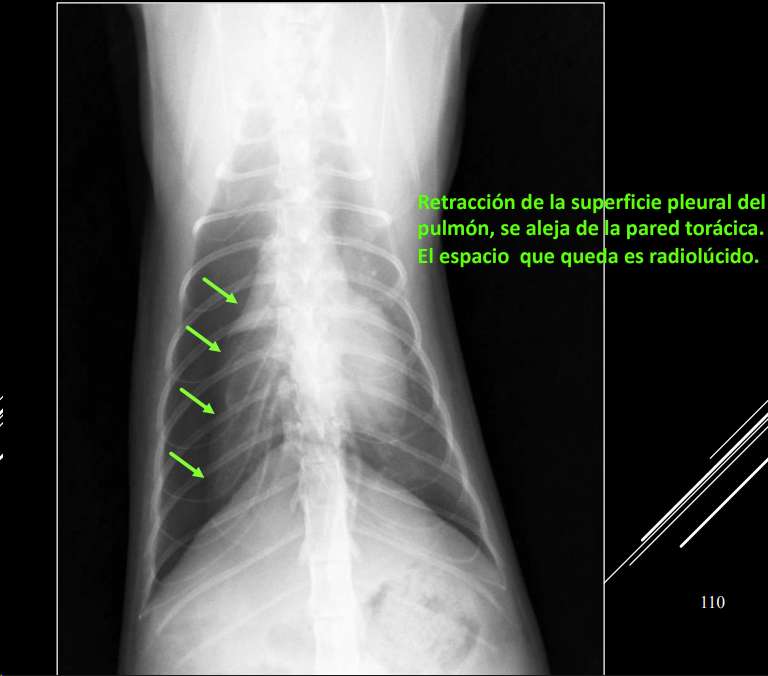

Neumotórax

- Aire en cavidad pleural.

- RX:

- Trama pulmonar no llega a pared torácica.

- Espacio radiolúcido entre pulmón y pared.

Cuando hay un neumotorax, al retraerse el pulmon se presentara un patron alveolar. Si el aire puede ir a ambos lados las presiones se compensan, anotensión. Si solo entra y no sale aumentara la presion y tendremos un neumotorax atensión